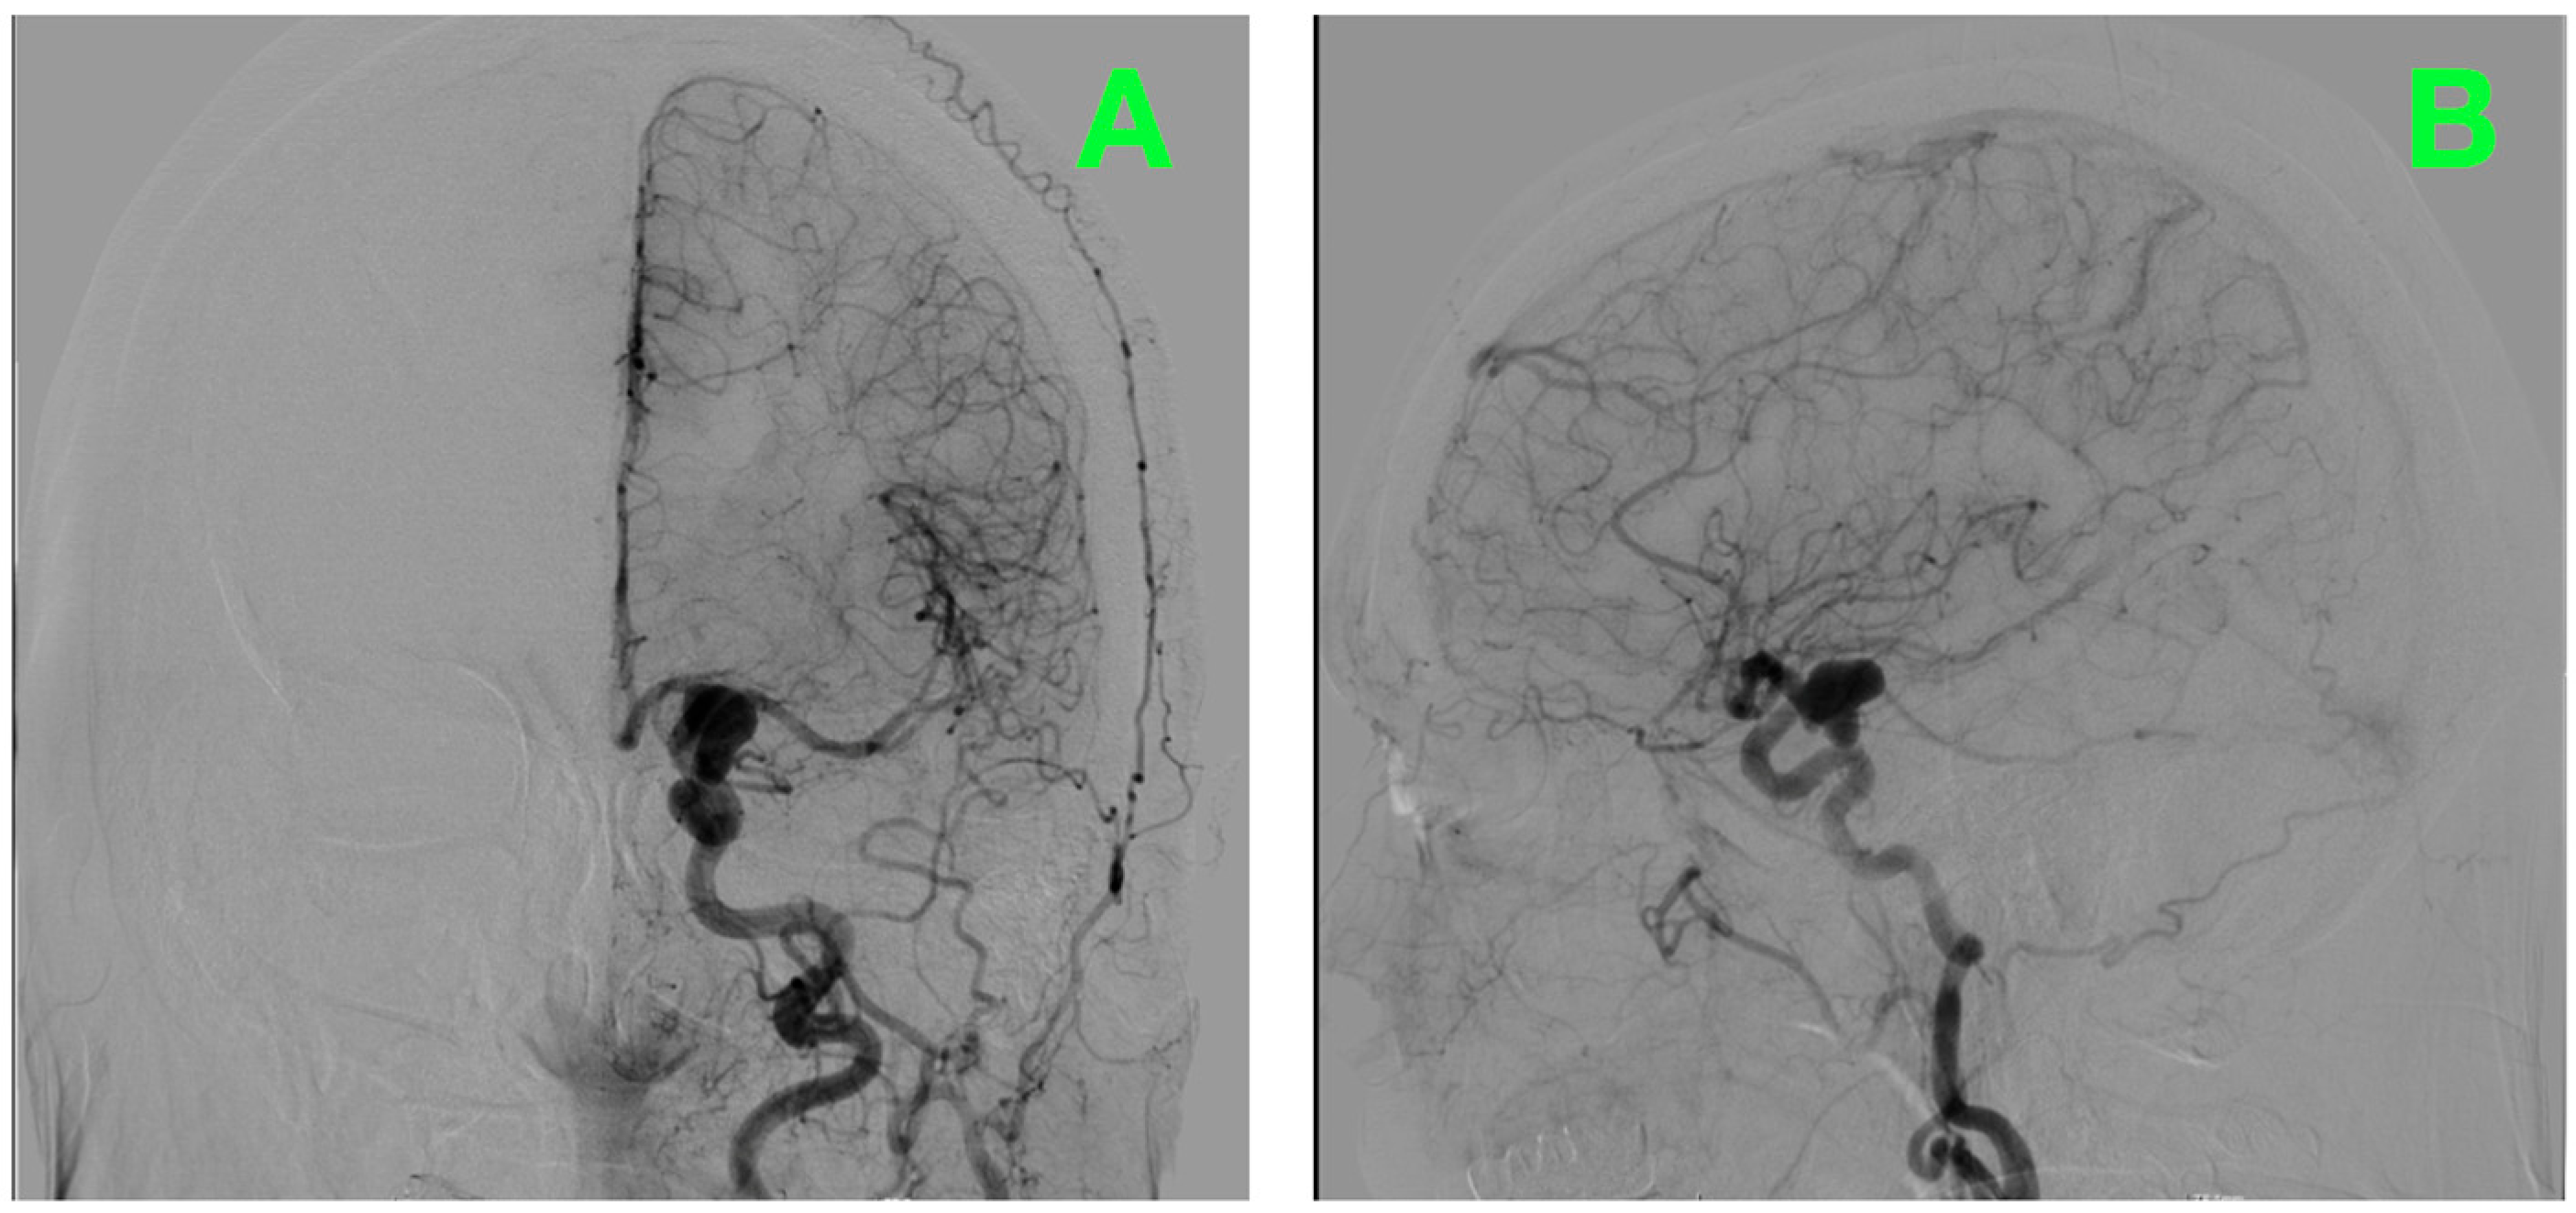

Catheter digital subtraction angiography (DSA) in anteroposterior oblique and lateral views (Figure 1A,B), supplemented by 3D rotational angiography (Figure 2A–D), demonstrated a left ICA-PCoA junction aneurysm originating from the communicating (C7) ICA segment and extending posteriorly into the carotid–optic cistern. Three-dimensional quantitative measurements of the aneurysm size demonstrated a maximum sac height of 13.1 mm, maximum sac width of 10.0 mm and maximum neck diameter of 4.3 mm, producing an aspect ratio of 3.06 and dome-to-neck ratio of 2.34. The aneurysm had a bilobed morphology with a smaller posterior superior daughter sac located along the posteromedial neck quadrant precisely adjacent to the PCoA origin and its associated perforator field—where even minimal posterior clip torque would pose a threat to the thalamoperforators.

Figure 1.

Diagnostic digital subtraction angiography of the left internal carotid artery. (A): Anteroposterior projection demonstrating a saccular aneurysm (arrow) arising from the ICA–posterior communicating artery (PCoA) junction on a caliber-preserved supraclinoid ICA. The PCoA is well-formed and originates at the aneurysm neck. On calibrated analysis the dome measures ~13 mm with a neck ~4.3 mm, projecting posteriorly into the opto-carotid cistern. Distal ACA and MCA branches opacify normally, with no angiographic vasospasm; the anterior choroidal artery opacifies separately and remains uninvolved. (B): Lateral projection confirming a posterior–superior dome trajectory with a bilobed contour. A compact perforator cluster is visualized posteromedial to the neck at the PCoA origin—an area corresponding to thalamoperforators and adjacent short circumflex branches—underscoring the need for a clip line that runs parallel to the PCoA take-off while preserving the anterior choroidal artery and perforator patency.